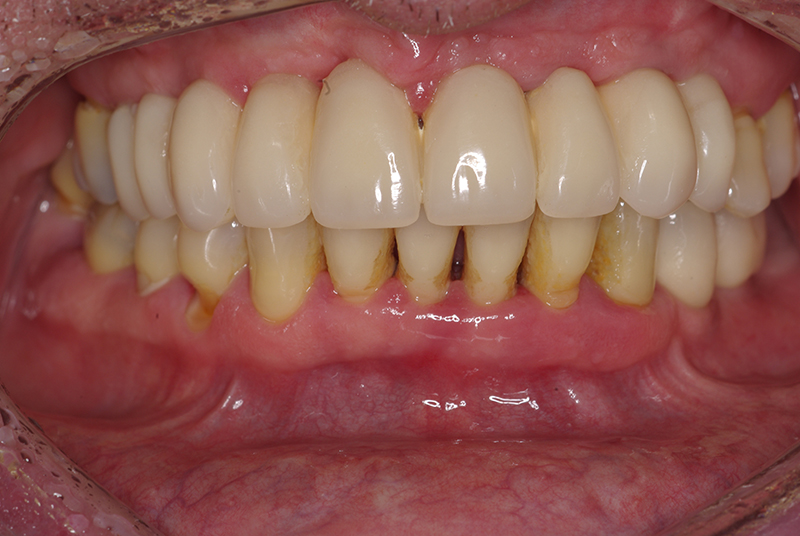

Na Clínica Pontes Odontologia, somos referência em implantes dentários em Fortaleza, oferecendo tratamentos de alta qualidade e tecnologia de ponta. Os implantes dentários são estruturas de titânio posicionadas cirurgicamente no osso maxilar ou mandibular para substituir as raízes dos dentes ausentes. Essa técnica permite a fixação de próteses personalizadas, restaurando a função mastigatória, a estética e a autoestima dos nossos pacientes.

Utilizamos a tecnologia CAD CAM, um sistema avançado que possibilita a confecção precisa das próteses dentárias diretamente sobre os implantes. Esse método inovador garante um ajuste perfeito, um resultado estético superior e proporciona muito mais conforto e durabilidade. Com o CAD CAM, nossos pacientes contam com um processo mais rápido e previsível para alcançar o sorriso desejado.